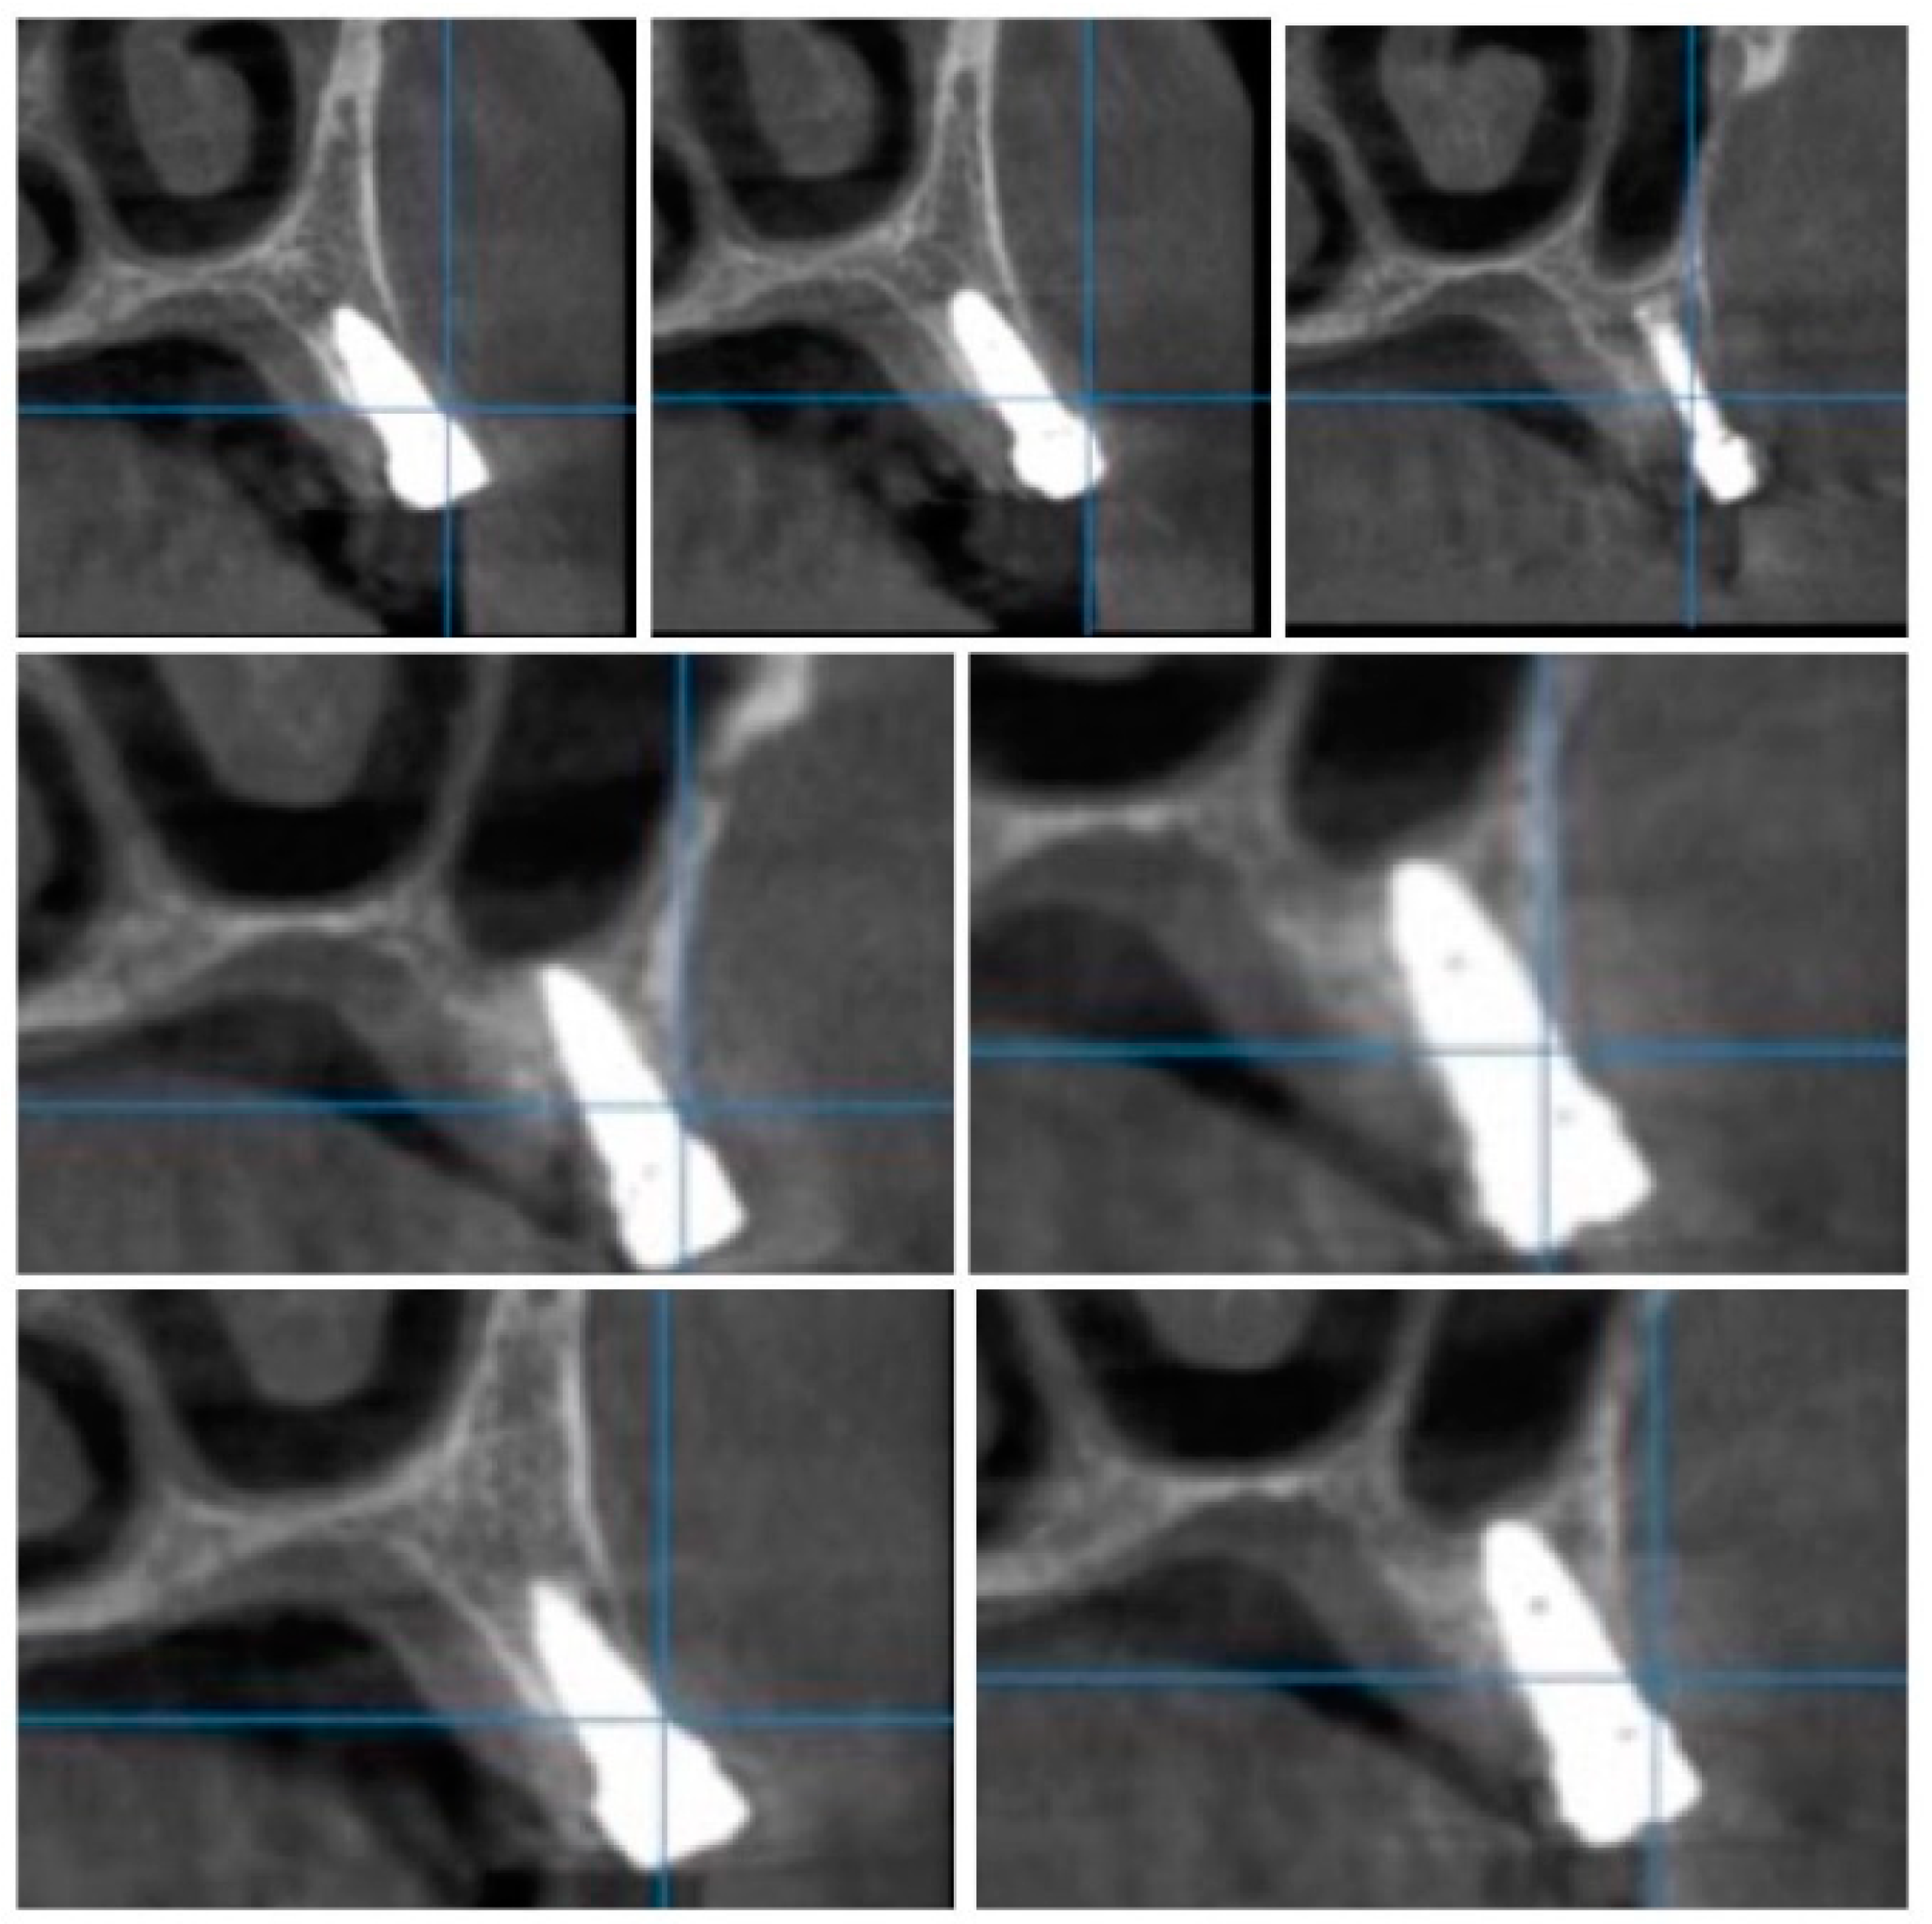

Figure 4.

CBCT images used in the study showing the density of bone.

Figure 5.

Image showing the bone density measured in Hounsfield units (HU) as well as the standard deviations of the volume.

Each voxel of the CBCT volume is characterized by a CT number, expressed in HU (Hounsfield Units). The software displays the mean value of the CT numbers of the constituent voxels and the standard deviation of these CT numbers (Figure 5).